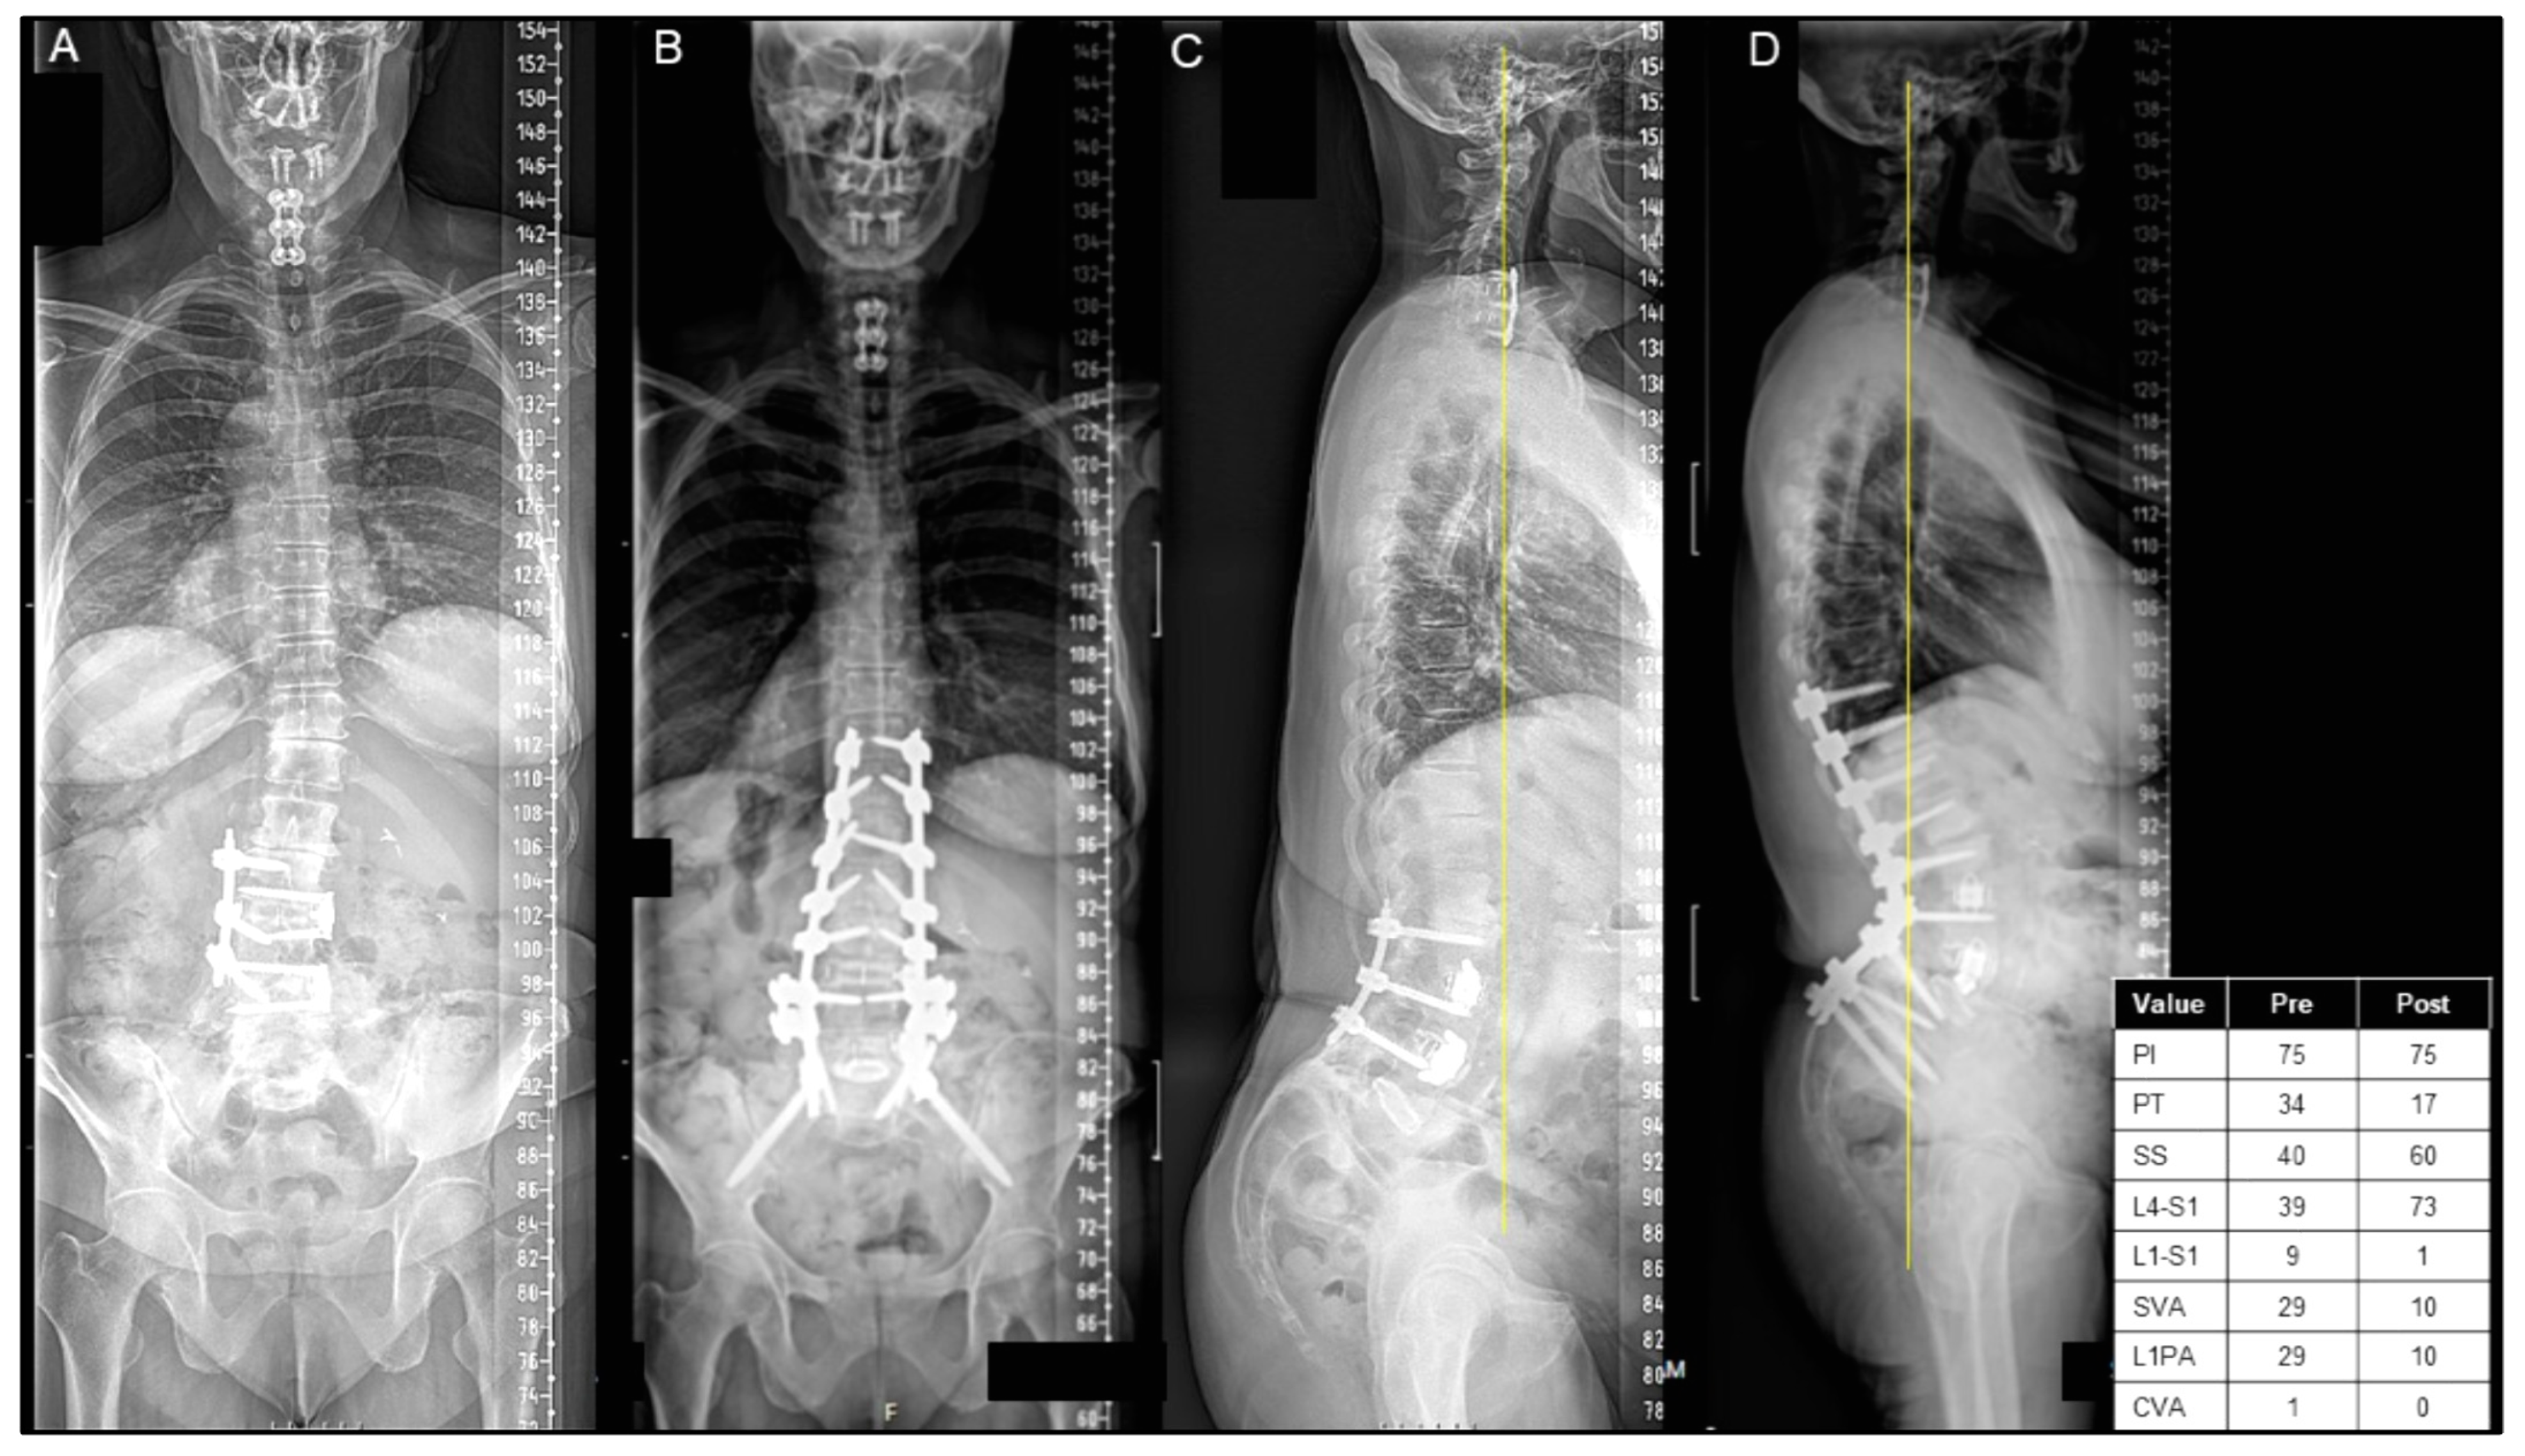

Figure 2.

(A–D) A case presentation of a 61-year-old female with a history of an L5/S1 high-grade spondylolisthesis in situ fusion as a teenager and an L3–5 lateral fusion as an adult, presenting with back and leg pain and significant sagittal/coronal malalignment, as seen on posterior–anterior (PA) (A) and lateral X-rays (C). The patient underwent T10 pelvis posterior spinal instrumentation with an L4 PSO, as seen on postoperative PA (B) and lateral X-rays (D). The patient was discharged to IPR on postoperative day 7.